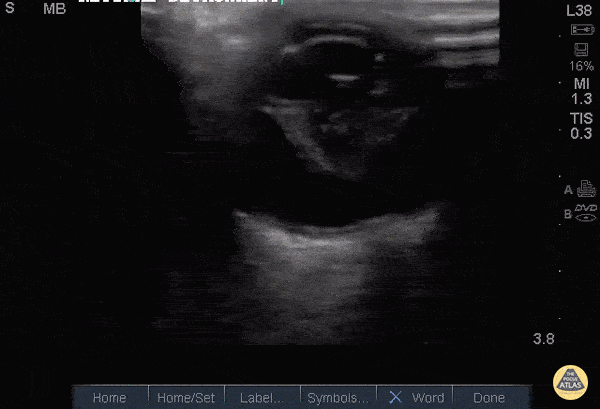

Orbital - Retinal Detachment with Vitreous Hemorrhage

34 y/o M with acute, atraumatic, painless, complete vision loss in the right eye x3 days, with an eye exam showing opacification of the right pupil and no light/dark perception. Ocular POCUS revealed a complete retinal detachment (RD) with a classic funnel shape. The funnel shape is caused by strong attachments of the retina to the optic nerve posteriorly, and to the ora serrata anteriorly. POCUS has been shown to have sensitivity 91-100% and specificity 68-96% for RD. In this image, the hyperechoic area within the funnel suggests an associated vitreous hemorrhage (VH), 30% of which are caused by retinal tears (RT). In fact, in patients with fundus-obscuring VH like our patient, 67% and 39% will have an associated RT or RD, respectively. Dr. Theodore J. Segarra, Dr. Stephanie Garcia, Dr. Nayla Delgado-Torres. SUNY Downstate/Kings County Emergency Medicine.